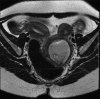

Figure 1c

Coronal image – Collection compressing the normal patent vagina on right side (open arrow)